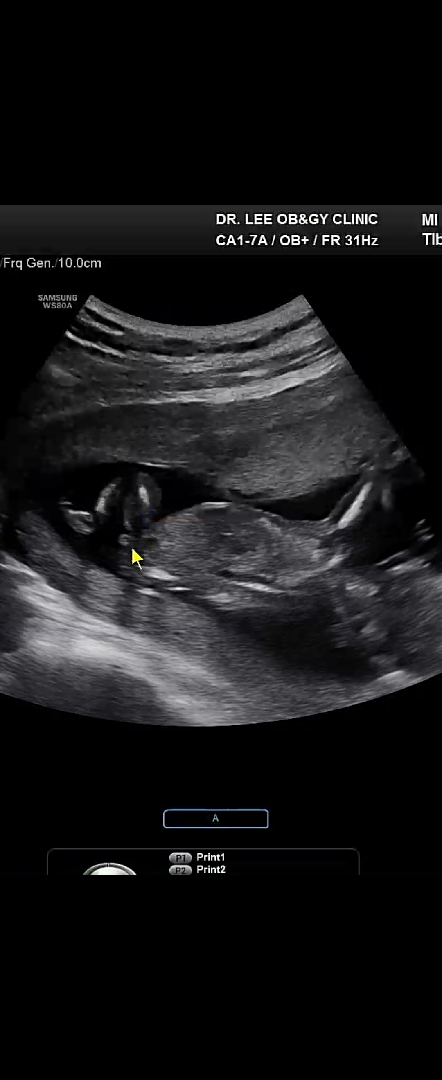

14주 5일차 아기 성별봐주세욤~

이게 딸래미 삼지창이라는게 맞을까요..? 딸같기도 한데!! 화살표 부분이요!